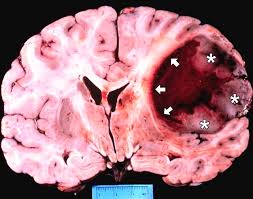

Glioblastoma: Killer cocktail combatte il cancro al cervello

Una nuova combinazione di farmaci che agiscono sul sistema immunitario, sradica una forma aggressiva di cancro al cervello, il glioblastoma,…